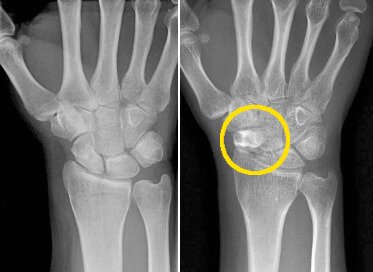

사진 왼쪽은 정상 손목, 오른쪽은 표시된 부분이 주상골로 불유합이 일어나면서 옆의 다른 손목뼈들의 위치가 붕괴된 것© News1